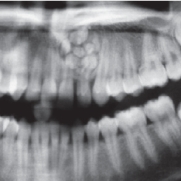

Una ricerca ha valutato l’efficacia di uno strumento prognostico nel prevedere gli esiti di guarigione dopo estrazione dentaria in pazienti medicalmente compromessi